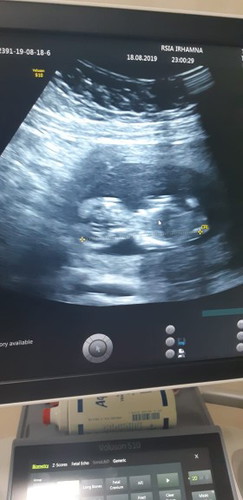

Janin umur 11 week 5 day

Alhamdulillah janinku sudah kelihatan seperti bayi utuh.. De2 utun sangat aktif dan lincah pas lagi di usg.. Do'ain ya bunda2 mudah2han sehat sampai lahir nanti dan sempurna tidak kekurangan satu apapun... Aamiin ya Allah?